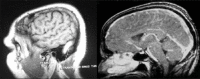

Figure 1

Magnetic resonance imaging brain venogram showing transverse sinus thrombosis and superior sagittal sinus thrombosis evidenced by empty delta sign